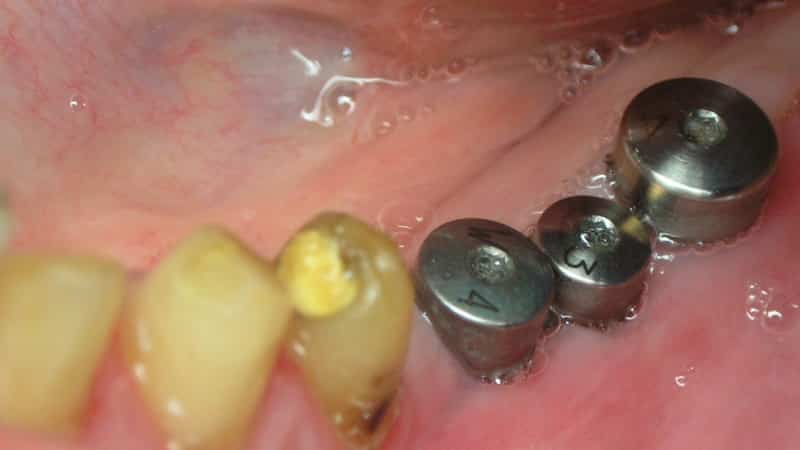

Первый тип формирователей десны — это первичные формирователи. Они устанавливаются сразу после имплантации и служат для создания необходимого объема и формы десны вокруг имплантата. Эти формирователи имеют различные размеры и формы, что позволяет стоматологу выбрать наиболее подходящий вариант в зависимости от клинической ситуации и анатомических особенностей пациента.

Второй тип — вторичные формирователи. Они используются на более поздних этапах лечения, когда необходимо скорректировать форму десны после заживления. Эти формирователи могут быть более тонкими и гибкими, что позволяет добиться более точной настройки десневой линии и улучшить эстетический результат.

Кроме того, формирователи десны могут различаться по материалу изготовления. Наиболее распространенными являются титановый и полимерный формирователи. Титановый материал обеспечивает высокую прочность и долговечность, в то время как полимерные формирователи могут быть более удобными в использовании и обеспечивать лучший контакт с мягкими тканями.